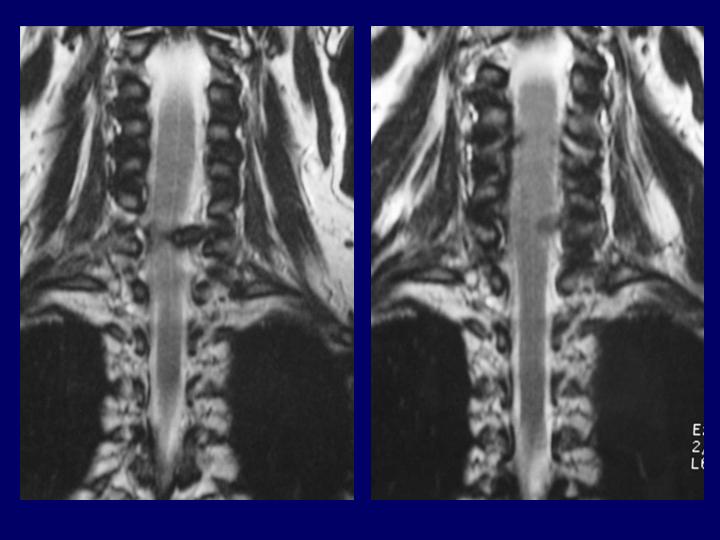

Hernias Discales